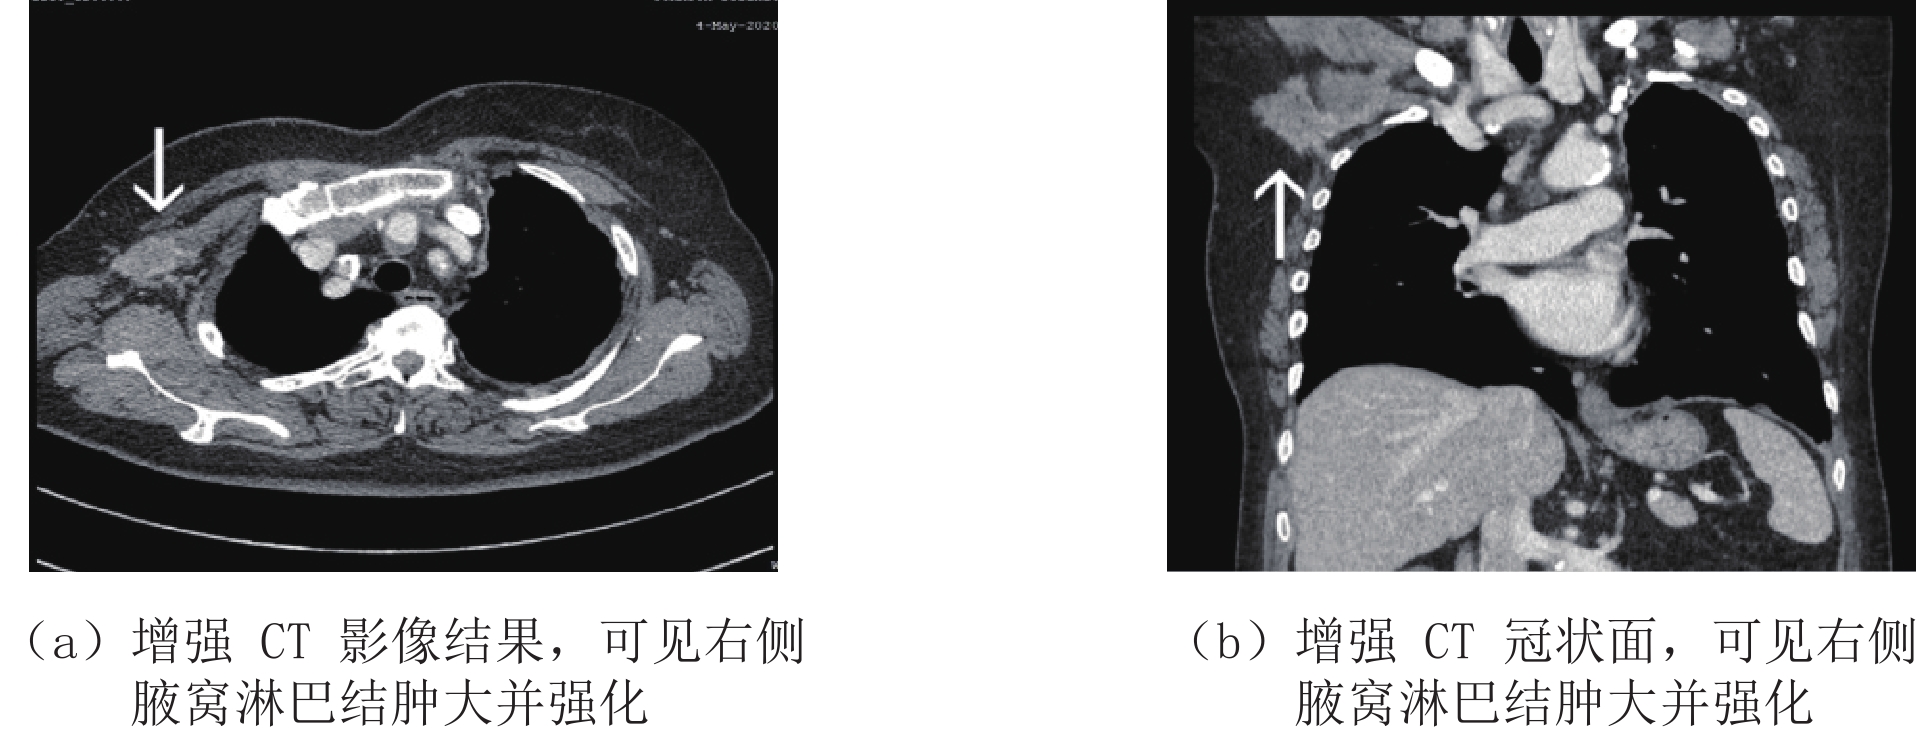

目的:探讨增强CT联合血清人乳腺珠蛋白(hMAM)水平检测对乳腺癌腋窝淋巴结转移的诊断价值。方法:选取2017年6月至2020年6月之间我院就诊并行手术治疗的乳腺癌患者100例,所有患者术前均行增强CT,并检测血清hMAM水平,以术后病理结果为标准,比较增强CT、血清hMAM水平单独检查及联合检查对腋窝淋巴结转移的检出率,分析其与病理结果的一致性,进一步分析增强CT联合血清hMAM水平对乳腺癌腋窝淋巴结转移的诊断价值。结果:血清hMAM和病理结果共同诊断为腋窝淋巴结转移阳性的患者51例(51%),血清hMAM和病理结果共同诊断为腋窝淋巴结转移阴性的患者12例(12%),一致率81.5%,Kappa检验一致性良好;增强CT和病理结果共同诊断为腋窝淋巴结转移阳性的患者55例(55%),增强CT和病理结果共同诊断为腋窝淋巴结转移阴性的患者13例(13%),一致率82.3%,Kappa检验一致性良好;增强CT联合血清hMAM检查和病理结果共同诊断为腋窝淋巴结转移阳性的患者61例(61%),增强CT联合血清hMAM检查和病理结果共同诊断为腋窝淋巴结转移阴性的患者16例(16%),一致率90.4%,Kappa检验一致性良好;增强CT和血清hMAM对淋巴结转移检出的灵敏度分别78.0% 和76.5%,特异度分别69.5% 和70.3%,差异不具有显著性,增强CT联合血清hMAM对淋巴结转移检出的灵敏度、特异度明显高于两者单独检查,差异具有统计学意义。结论:增强CT联合血清hMAM水平对乳腺癌腋窝淋巴结转移具有较高的诊断价值,和病理结果比较一致性高,乳腺癌术前综合检查、全面分析,有利于疾病的诊断,对于手术方式的选择提供依据。

Abstract:Objective: To investigate the diagnostic value of enhanced CT combined with serum human mammaryglobin (hMAM) level in detection of axillary lymph node metastasis of breast cancer. Methods: 100 patients with breast cancer treated in our hospital from June 2017 to June 2020 were selected. All patients underwent enhanced CT before operation, and the serum hMAM level was detected. We further analyzed the diagnostic value of enhanced CT combined with serum hMAM level in axillary lymph node metastasis of breast cancer by comparing the consistency between the results of the detection rate of axillary lymph node metastasis obtained respectively by enhanced CT, serum hMAM level, combined examination and the postoperative pathological results which was taken as the standard. Results: 51 patients (51%) were diagnosed as positive axillary lymph node metastasis by serum hMAM and pathological results while 12 patients (12%) with negative axillary lymph node metastasis were diagnosed by both serum hMAM and pathological results, with the consistency rate of 81.5%. Kappa test showed great consistency, 55 cases (55%) were diagnosed as positive axillary lymph node metastasis by enhanced CT and pathological results while 13 cases (13%) with negative axillary lymph node metastasis were diagnosed by enhanced CT and pathology, with the consistency rate of 82.3%. Kappa test showed great consistency, There were 61 cases (61%) with positive axillary lymph node metastasis diagnosed by enhanced CT combined with serum hMAM examination and pathological results while 16 cases (16%) with negative axillary lymph node metastasis diagnosed by enhanced CT combined with serum hMAM examination and pathological results, with the consistency rate of 90.4%. Kappa test showed great consistency, The sensitivity of enhanced CT and serum hMAM were respectively 78.0% and 76.5% while the specificity were respectively 69.5% and 70.3%, which showed no significant difference. The sensitivity and specificity of enhanced CT combined with serum hMAM in detecting lymph node metastasis were significantly higher than those of the two alone. Conclusion: The method of enhanced CT combined with serum hMAM level hold high diagnostic value for axillary lymph node metastasis of breast cancer, and show high consistency with the pathological results. Preoperative comprehensive examination and comprehensive analysis of breast cancer are conducive to the diagnosis of the disease and can provide basis for the selection of surgical methods.